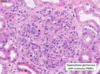

Wilms tumor Microscopic features (3)

- Triphasic pattern*

- Primitive blastema (small/dark undifferentiated cells)

- Epithelial component (abortive tubules/glomeruli)

- Stroma (Fibrous or myxoid patterns; may contain mesenchymal elements (cartilage, muscle, bone)

Wilms tumor microscopic features (3):

Triphasic pattern

- Primitive blastema (small/dark undifferentiated cells)

- Epithelial component (abortive tubules/glomeruli)

- Stroma (Fibrous or myxoid patterns; may contain mesenchymal elements (cartilage, muscle, bone)